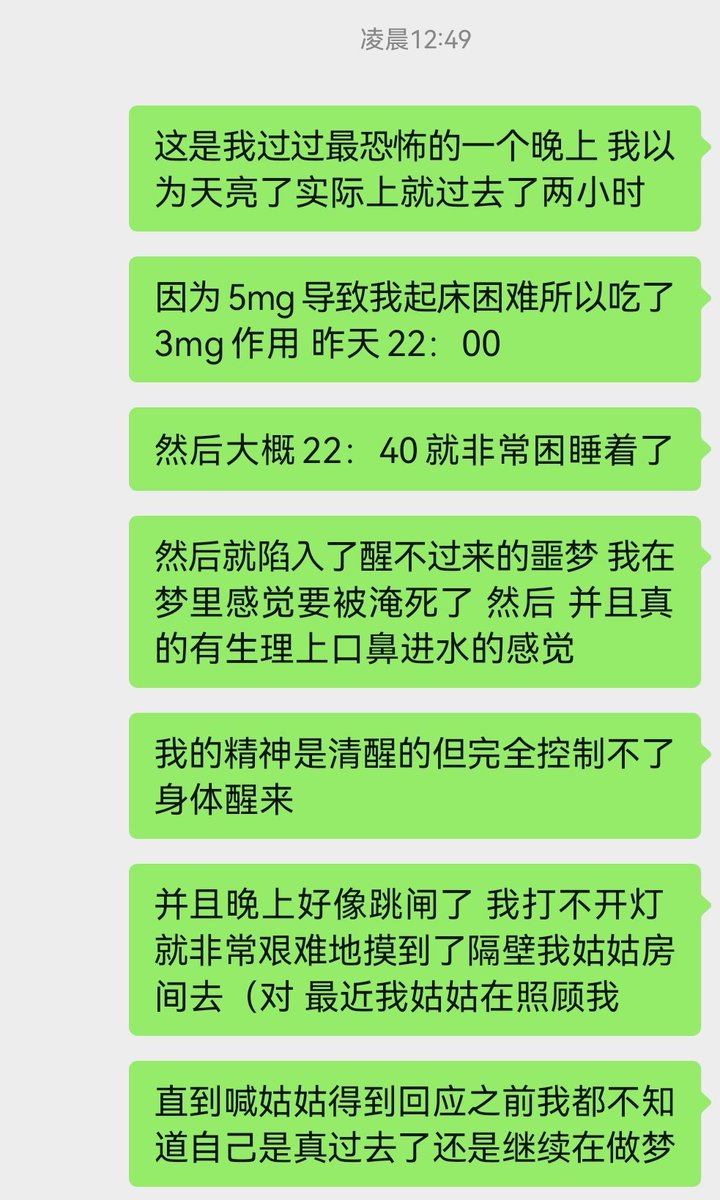

2026-01-09 07:42:08 UTC

今天起来特别晕,完全不知道是怎么回事,以为是昨天测试物质的副作用我在想这么恐怖,然后怀疑今天是不是丁螺环酮吃了两次,直到我去看用药记录。。

好家伙唑吡坦又骗我吃药了还顺带上了个失忆状态,这下子知道是谁干的了。吃auv之后dxm清除得特别慢...让我感觉要从此告别了的程度,加上我基因检测本来cyp2d6就是中速代谢,这个尾巴就被拖的特别长

想起来昨天是因为完全看不懂字了什么都干不了才睡觉的,还好没去骚扰别人()

炽烈已极 @AnIncandescence@oct424242 实际上我判断这是dxm干的,真相大白了

炽烈已极 @AnIncandescence醒了躺在床上的时候想着怎么还有内幻呢,像是在拉摇杆操纵游戏里的小人,以一个俯瞰的视角(经典)

睁眼和闭眼没什么区别,整个身体都是飘起来的,直到现在还重力异常。。感觉能持续24h https://t.co/KcnvEYrDOG[图片媒体不可用]

炽烈已极 @AnIncandescence迷迷糊糊的平白无故很开心,想着原来冬天睡觉这么舒服的吗在被子里蛄蛹()后来真相大白是刷出欣快tag了,robo就是比较容易出